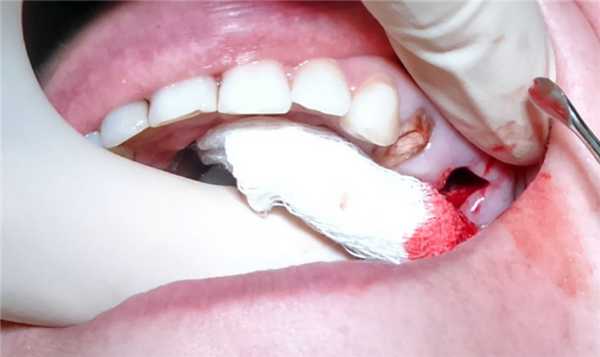

Безоперационное лечение ороантрального соустья возможно только в случае его немедленного обнаружения. Если прободение дна пазухи произошло во время экстракции зуба, необходимо приложить все усилия для сохранения в лунке кровяного сгустка. С этой целью устанавливается йодоформная турунда или накладывается альвеолярная повязка (альвожил, альвостаз), которая фиксируется швами. Возможно закрытие раны фибриновым или тканевым клеем, фибриновой пленкой, защитными пластинками.

Назначается медикаментозная терапия, направленная на предупреждения инфицирования: антибиотики, антигистаминные, закапывание сосудосуживающих капель в нос. В течение недели пациенту следует избегать чихания, кашля, сморкания. При соблюдении рекомендаций за это время перфорация до 2-5 мм закрывается самостоятельно.

Сформировавшиеся ороантральне фистулы диаметром более 5 мм, протекающие свыше 3-х недель, требуют хирургического вмешательства. Если во время перфорации в полость пазухи проникли инородные тела, выполняется гайморотомия, удаление посторонних предметов и измененных тканей с последующей пластикой перфоративного отверстия. Все операции делятся на 3 группы:

- пластика местными тканями: мобилизация, перемещение и подшивание к краям раны альвеолярного, вестибулярного, щечного или комбинированного лоскута;

Если перфорация осложнена разрывом десны и пенетрацией инородных частиц в мягкие ткани, окружающие лунку зуба, выполняют пластическое закрытие дефекта в этот же день. Или через некоторое время, когда будет уверенность, что ткани будут держать швы. Перед этим удаляют все инородные тела и иссекают участки, подвергшиеся некрозу. Манипуляцию выполняют под рентген контролем, чтобы удостовериться, что там нет инородного тела. Если произошло проникновение в полость инородного тела, то необходимо делать операцию в условиях стационара.